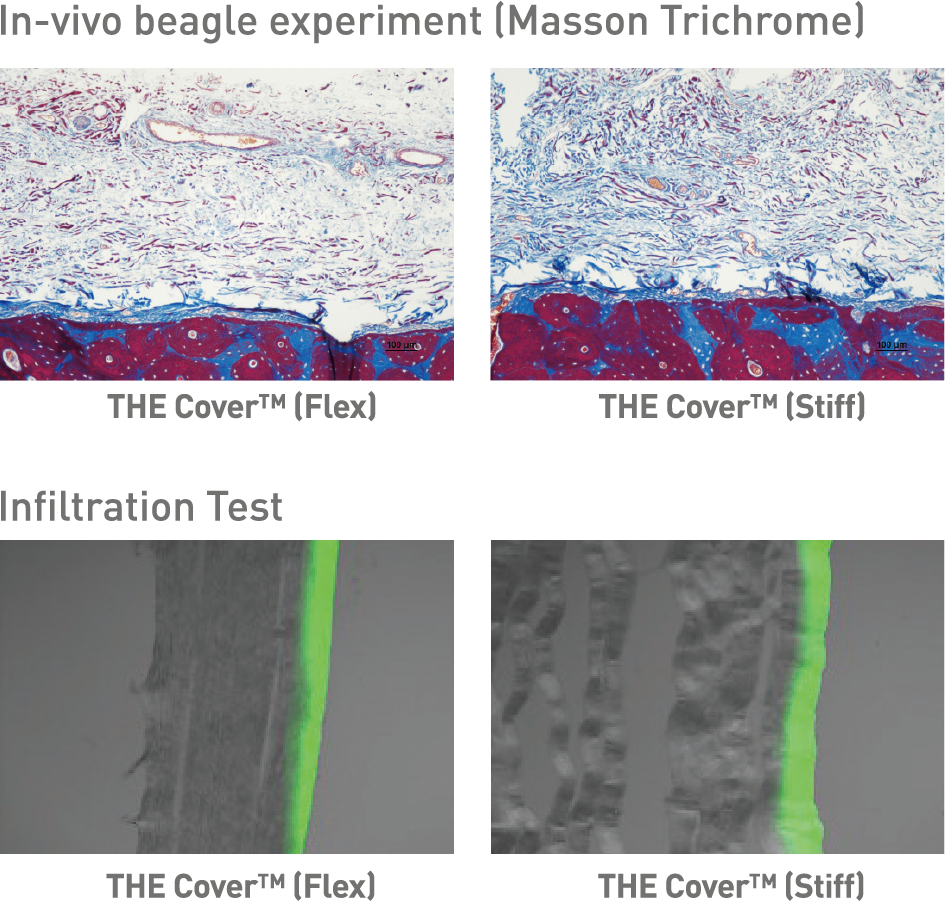

Er zijn twee varianten beschikbaar:

THE Cover™ Flex – voor optimale flexibiliteit en een bijzonder gebruiksvriendelijke handling.

THE Cover™ Stiff – met verhoogde stijfheid, ideaal voor betrouwbare ruimtebehoud.